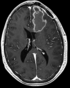

Case 27: DTI baseline to FLAIR/T1 pair, large pathol.

Case 29: DTI to T1 / Alignment of DTI and fMRI scan to structural reference T2/T1 pair for surgical planning (tumor resection)

Case 30: lowres & small FOV DTI to T1, no T2

Case 33: DTI baseline to T1, incl. pathol.